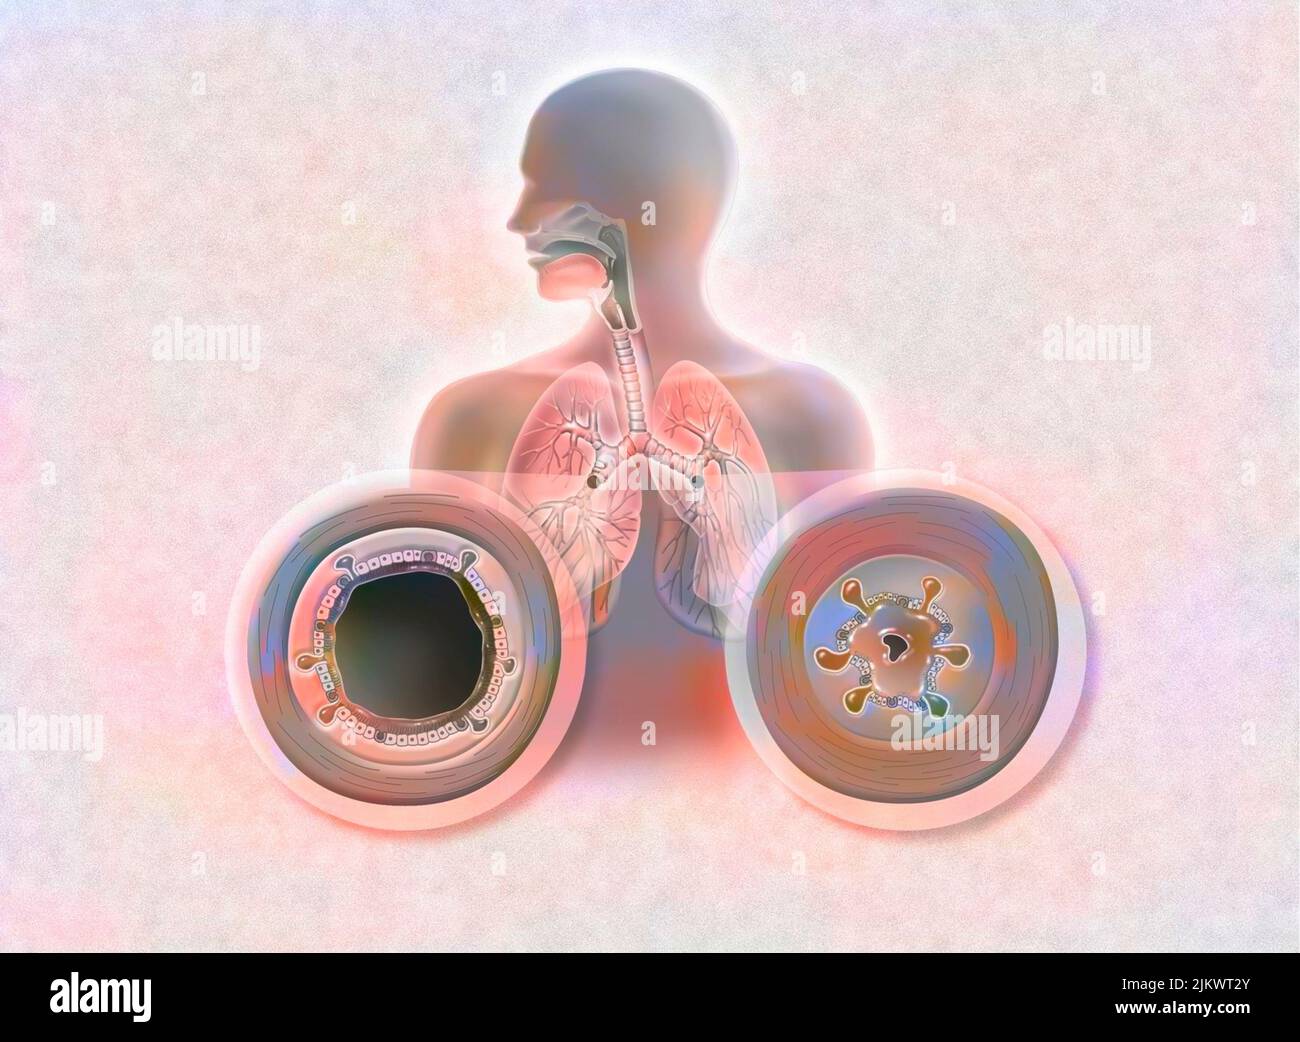

Effect of the bronchodilator on a bronchus with an asthma attack (left) and COPD (right). Stock Photohttps://www.alamy.com/image-license-details/?v=1https://www.alamy.com/effect-of-the-bronchodilator-on-a-bronchus-with-an-asthma-attack-left-and-copd-right-image476926507.html

Effect of the bronchodilator on a bronchus with an asthma attack (left) and COPD (right). Stock Photohttps://www.alamy.com/image-license-details/?v=1https://www.alamy.com/effect-of-the-bronchodilator-on-a-bronchus-with-an-asthma-attack-left-and-copd-right-image476926507.htmlRF2JKWTHF–Effect of the bronchodilator on a bronchus with an asthma attack (left) and COPD (right).

Bronchodilator on a bronchus with an asthma attack and COPD. Stock Photohttps://www.alamy.com/image-license-details/?v=1https://www.alamy.com/bronchodilator-on-a-bronchus-with-an-asthma-attack-and-copd-image476923686.html

Bronchodilator on a bronchus with an asthma attack and COPD. Stock Photohttps://www.alamy.com/image-license-details/?v=1https://www.alamy.com/bronchodilator-on-a-bronchus-with-an-asthma-attack-and-copd-image476923686.htmlRF2JKWN0P–Bronchodilator on a bronchus with an asthma attack and COPD.

Effect of the bronchodilator on a bronchus with an asthma attack (left) and COPD (right). Stock Photohttps://www.alamy.com/image-license-details/?v=1https://www.alamy.com/effect-of-the-bronchodilator-on-a-bronchus-with-an-asthma-attack-left-and-copd-right-image476926523.html

Effect of the bronchodilator on a bronchus with an asthma attack (left) and COPD (right). Stock Photohttps://www.alamy.com/image-license-details/?v=1https://www.alamy.com/effect-of-the-bronchodilator-on-a-bronchus-with-an-asthma-attack-left-and-copd-right-image476926523.htmlRF2JKWTJ3–Effect of the bronchodilator on a bronchus with an asthma attack (left) and COPD (right).

Bronchodilator on a bronchus with an asthma attack and COPD. Stock Photohttps://www.alamy.com/image-license-details/?v=1https://www.alamy.com/bronchodilator-on-a-bronchus-with-an-asthma-attack-and-copd-image476923650.html

Bronchodilator on a bronchus with an asthma attack and COPD. Stock Photohttps://www.alamy.com/image-license-details/?v=1https://www.alamy.com/bronchodilator-on-a-bronchus-with-an-asthma-attack-and-copd-image476923650.htmlRF2JKWMYE–Bronchodilator on a bronchus with an asthma attack and COPD.